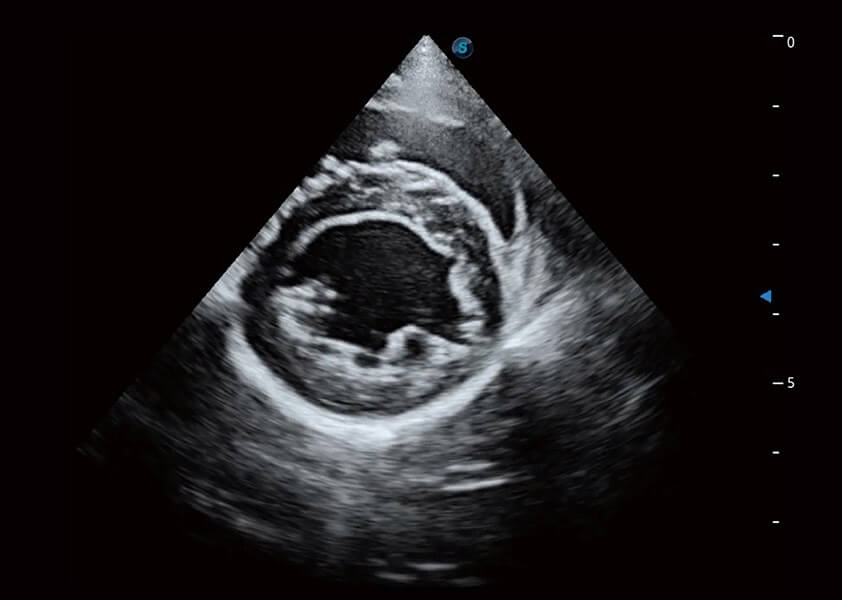

(犬)乳头肌短轴